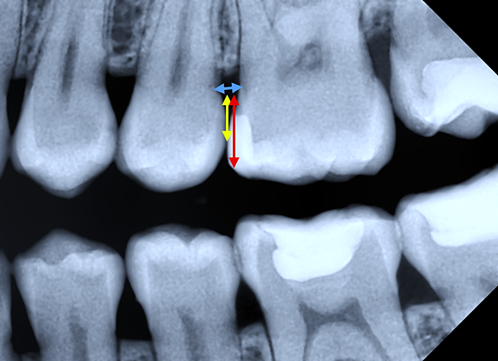

For lateral teeth, where the contact area is anatomically positioned at the maximum contour of the proximal surfaces and at the transition between the middle and occlusal third of the cervico-occlusal distance, three distances were calculated (Fig. 5):

distance between adjacent teeth at the cemento-enamel junction (CEJ);

distance from the CEJ to the middle of the contact area;

distance from the CEJ to the occlusal edge, along the cervico-occlusal distance.

To calculate the middle of the cervico-occlusal distance, the following formula was applied:

To calculate the occlusal third of the cervico-occlusal distance, the following formula was applied:

Thus, the anatomical positioning of the interdental contact was considered to fall within the interval between the point representing the middle of the cervico-occlusal distance and the point representing 2/3 of the cervico-occlusal distance, calculated from the cervical level.

|

Fig.5 Bitewing radiography. Distances measurements. Note: Blue line - distance between adjacent teeth at the cemento-enamel junction (CEJ). Yellow line - distance from the CEJ to the middle of the contact area. Red line - distance from the CEJ to the occlusal edge, along the cervico-occlusal distance. |